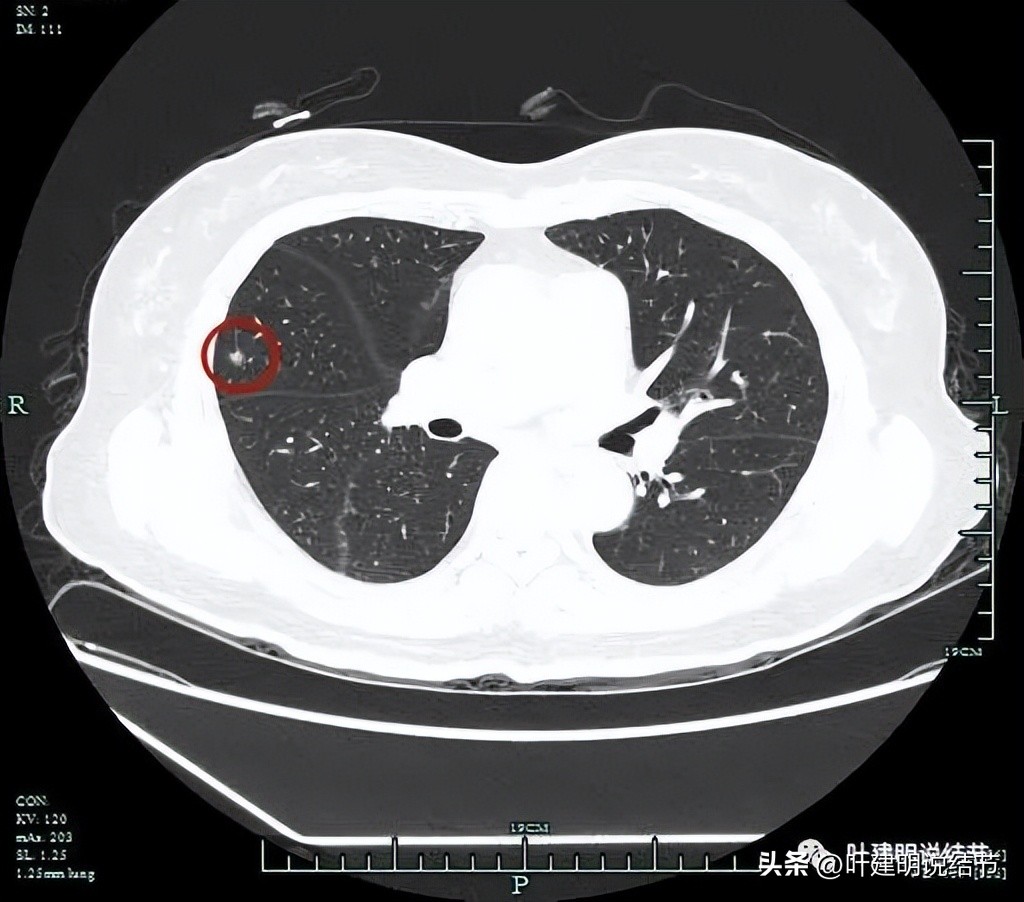

磨玻璃成分也是明显的。

靶扫描重建图像显示了病灶明显的血管进入(如桔色箭头所示),灶内似见进入血管的穿行,而且显得毛糙与异常增粗。